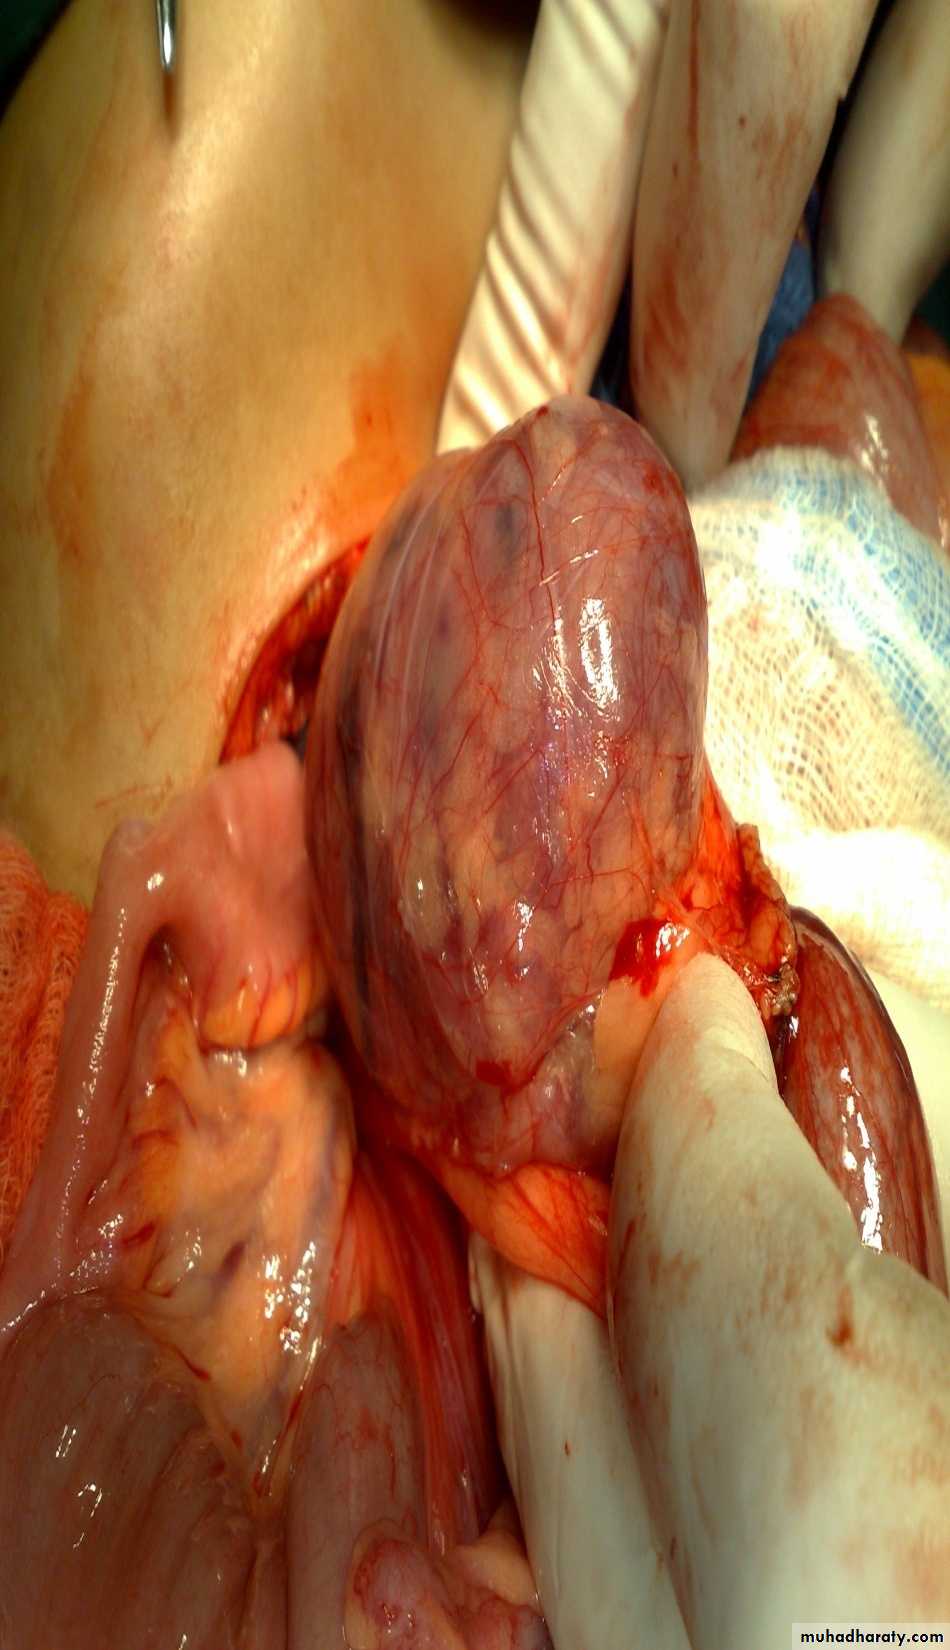

Abdominal Wall Defects

Defect=sac